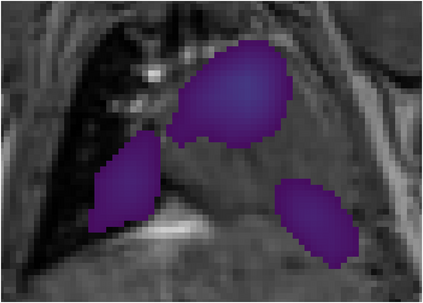

Various imaging modalities allow for time-dependent image reconstructions from measurements where its acquisition also has a time-dependent nature. Magnetic particle imaging (MPI) falls into this class of imaging modalities and it thus also provides a dynamic inverse problem. Without proper consideration of the dynamic behavior, motion artifacts in the reconstruction become an issue. More sophisticated methods need to be developed and applied to the reconstruction of the time-dependent sequences of images. In this context, we investigate the incorporation of motion priors in terms of certain flow-parameter-dependent PDEs in the reconstruction process of time-dependent 3D images in magnetic particle imaging. The present work comprises the method development for a general 3D+time setting for time-dependent linear forward operators, analytical investigation of necessary properties in the MPI forward operator, modeling aspects in dynamic MPI, and extensive numerical experiments on 3D+time imaging including simulated data as well as measurements from a rotation phantom and in-vivo data from a mouse.